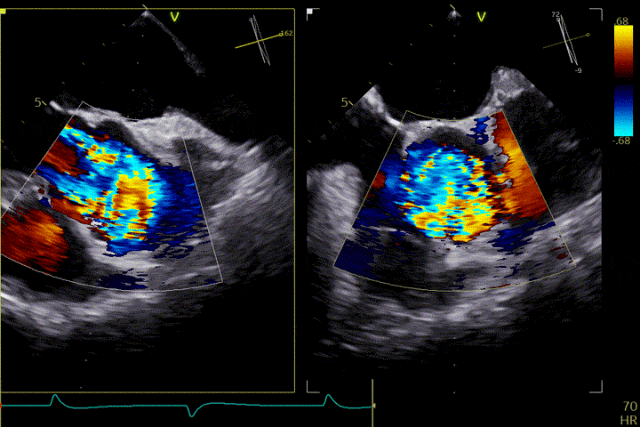

輸送器跨瓣

打開定位件

定位件入竇

瓣膜釋放